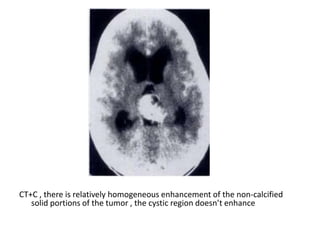

CT+C , there is relatively homogeneous enhancement of the non-calcified

solid portions of the tumor , the cystic region doesn’t enhance